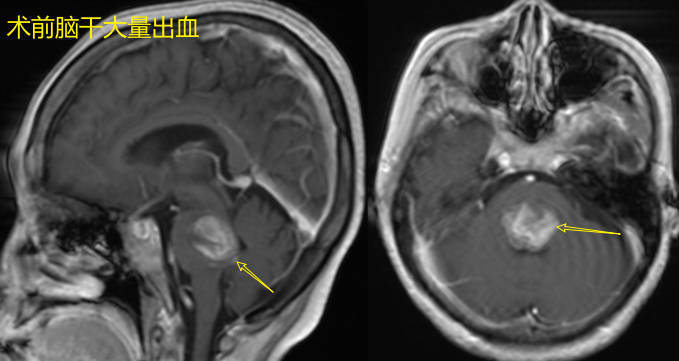

脑内海绵状血管瘤实际不是真正的肿瘤,而是“血管畸形”的一种。为神经外科比较常见的一个疾病。请注意脑外海绵状血管瘤和脑内海绵状血管瘤不是同一个疾病。比如海绵窦海绵状血管瘤就是一个特殊的疾病你。脑内海绵状血管瘤实际是众多薄壁血管组成的海绵状异常血管团。主要表现是畸形血管不断反复出血,出血又不断溶解吸收,但吸收不完全,导致局部病灶不断增大,增大过程可以非常缓慢,甚至几十年变化不明显,很少发生致命性大出血。打个比方,好比有个金属自来水管,间歇性渗水,水又被风干吸收,这样漏水处局部有锈蚀团块不断增大,速度不一。相当一部分患者为多发性海绵状血管瘤,即脑内不止一处病灶,有2个或2个以上病灶,有的病灶非常多,似“满天星”。部分患者有家族遗传史。1.慢性头痛:发作间期不一定,头痛轻微甚至不被重视;2.癫痫:不同形式的表现,如肢体不自主抽动、突发一过性意识丧失、肢体发作性麻木、嗅幻觉、视幻觉、听幻觉等等。1.头颅CT:常见为脑内高密度灶2.头颅磁共振平扫、增强、SWI(磁敏感):三者相结合基本可以确诊该病,并与其他肿瘤相鉴别。海绵状血管瘤有时与脑内黑色素瘤鉴别有一定困难。SWI(磁敏感):可以发现常规磁共振扫描不能发现的其他海绵状血管瘤的微出血灶。3.脑电图:辅助确定有无异常脑电波发放,就是癫痫波。下面是同一患者68岁(2023年)的头颅CT和磁共振,可见T2磁共振显示的海绵状血管瘤比CT多,SWI显示的更多(患者有脑干海绵状血管瘤)。患者并无头痛和癫痫症状,正常生活,其实他脑内这些海绵状血管瘤已经存在很多年了!其儿子2014年先发现有脑内多发性海绵状血管瘤,其中一处发生出血而手术,证实为海绵状血管瘤。其儿子2014年(27岁)因为突发头痛伴视物模糊发现“左枕叶出血,性质待定”手术切除左枕叶病灶,病理证实为“海绵状血管瘤”,其他病灶散在,无明显症状,无癫痫,随访观察即可。下面这位患者2015年发现海绵状血管瘤,无症状,因此无需任何处理,随访近9年无变化。合并的静脉畸形本身一般不会导致出血,而且它收集脑组织的静脉回流,因此手术时要尽量保护保留它。1.随访观察:对于偶然发现、无明显症状的,不做任何处理,定期复查磁共振即可;2.抗癫痫治疗:病灶位于重要功能区,有癫痫症状的患者,手术可能导致瘫痪的建议抗癫痫药物治疗观察3.手术切除病灶:病灶位于非功能区,导致反复出血头痛、癫痫症状的首选手术切除,可根治。4.放疗有争议,多数认为无效,可造成放射性损伤,并可诱发新的海绵状血管瘤!(下文有案例)5.无药物可以治疗使得海绵状血管瘤缩小或消失!下面这个67岁男性,右侧脑室旁海绵状血管瘤,其实可以不用任何治疗,但患者被推荐选择伽马刀放疗后3月,出现放疗性水肿。下面这个女孩2017年因为右侧肢体不灵活,发现左基底节海绵状血管瘤,考虑病灶继续长大将导致瘫痪,我予以手术,术后肢体肌力逐渐好转。2023年7月来复诊,基本如常人。下面这个患者,突发头痛,发现脑室内海绵状血管瘤。我予以手术。术后3月恢复良好。为一个非常特殊的部位的海绵状血管瘤,是否手术争议较大!主要原因在于脑干内有主管头面部各种运动和感觉的核团,四肢感觉和运动的神经传导束经过,通俗的说就是有管理手脚活动与感觉的电线都从这里经过,而脑干的延髓只有拇指大小,神经密集。脑干部位的海绵状血管瘤出血可以压迫和破坏神经传导束和核团,出现肢体麻木,乏力、视物重影、行走不稳、喝水呛咳等表现,但是随着出血吸收,这些症状又可以逐渐缓解甚至基本消失。下一次再出血可以导致症状再现,如此症状反复。重要的是2次出血的时间间隔,出血量不能确定。患者从首次发现脑干海绵状血管瘤出血开始,到下一次发现出血症状之间可能数年甚至10~20年不等,而出血量多数不大!如果手术去清除脑干的海绵状血管瘤,必然对海绵状血管瘤周围的脑干内神经传导束或神经核团有不同程度的骚扰或破坏,有可能破坏是不可逆的,从而导致功能恶化。因此脑干海绵状血管瘤的手术与否争议较大!要权衡得失再定手术与否!1.对于靠近脑干表面的海绵状血管瘤,如反复出血或出血量大压迫神经,手术容易接近,首选手术。2.对于脑干内,离脑干表面较深在的病灶,一般选择观察,因为手术必然要切开脑干表面到达病灶,对脑干内神经传导束或神经核团有不同程度的骚扰或破坏,可能导致功能恶化,因此更倾向于观察。病例一、脑干海绵状血管瘤患者,女性,2020年30岁时发现脑干海绵状血管瘤,未手术随访观察,2020年6月1号与2024年1月27号磁共振对比,脑干的中脑处海绵状血管瘤出血大部分吸收,并无明显症状。继续随访观察。病例二、患者,女,38岁,头晕伴右侧肢体肌力下降检查发现海绵状血管瘤,病灶体积较大,且靠近脑干表面,已有肢体肌力下降,故建议手术切除。2022年12月14日我予以手术,全切病灶。术后出现暂时性左侧肢体肌力下降(因为手术必然对周围神经传导束有一定骚扰),因为神经传导束没有显著损伤,故之后逐渐恢复,无明显其他神经损伤等明显后遗症。术后近3月(2023年3月)门诊复查视频,行走自如。2024年1月复查磁共振及CT显示病灶无复发。术后1年门诊复查视频病例三、女性,2019年(56岁),头晕发现脑干背侧海绵状血管瘤,位置深在,当时症状不明显,随访观察,3年后(2022年)病灶增大,出现头晕加重行走不稳,当地医生推荐来我处就诊,和家属沟通风险后予以行病灶切除术,术后症状好转。2022年7月11日(术后一月)行走较自如2022年8月30号术后3月复查磁共振,显示海绵状血管瘤全切。